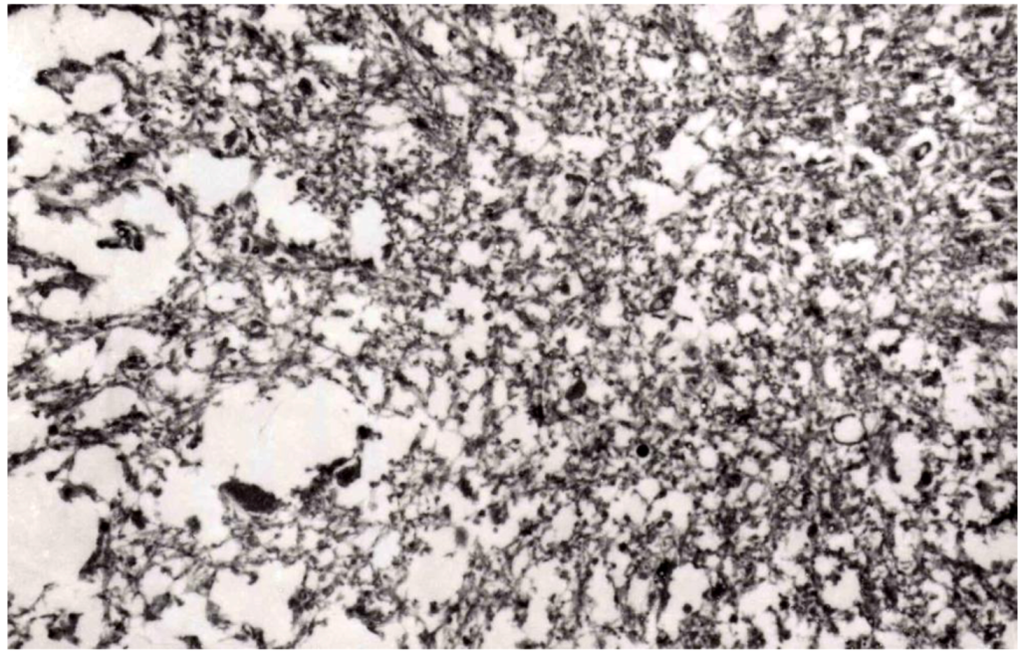

8. Neuropathology